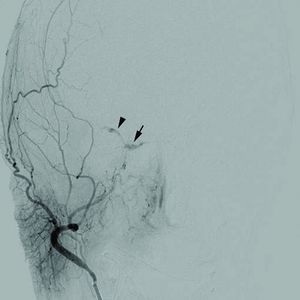

Cerebral angiogram of a carotid-cavernous fistula | |

كما تُدرس الأوعية الدموية التي تغذي الدماغ بوساطة الأمواج فوق الصوتية أو بطرق أخرى (كتصوير الشرايين بالقثطرة أو بالمرنان المغنطيسي). والهدف من ذلك كله تحديد ما إذا كان هناك شريان متضيق وبحاجة إلى التوسيع.

أما التشخيص فقد يعتمد على عدة إجراءات منها تصوير الدماغ (الطبقي المحوري وأحياناً المرنان المغنطيسي) أو إجراء بزل قطني لتحري وجود الدم في السائل الدماغي الشوكي. ومن الإجراءات المهمة تصوير الشرايين الدماغية (بوساطة القثطرة) للتحري عن وجود تشوهات وعائية.